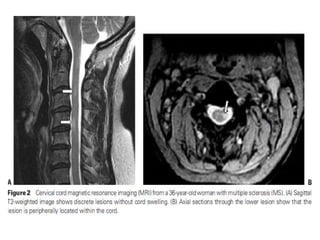

• a multifocal neurologic disease (eg, multiple

sclerosis, neuromyelitis optica, acute

• TM as a part of the spectrum of multiple sclerosis. In some cases,

TM is the initial demyelinating event (a clinically isolated syndrome

[CIS]) that precedes clinically definite multiple sclerosis.